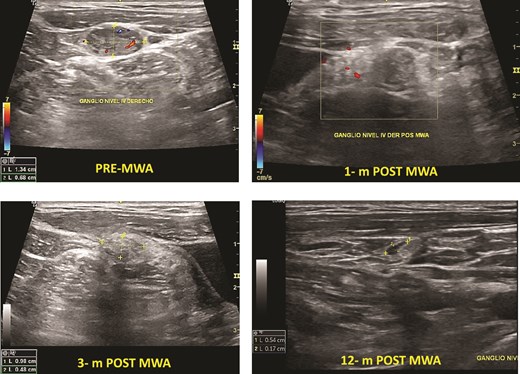

Two patients had cervical metastasis of PTC confirmed by PAAF. Both were on the right side located on level 4. The longest diameter of the ablated LNs reduced from 13.0 (SD 4.0) mm to 5.0 (SD 3.1) mm (P < .001) at 6-month follow-up. Furthermore, the overall mean volume pre-MWA was 0.32 (0.2) ml. After ablation, the mean TN volume at 1-month, 3-month, 6-month, and 12-month were 0.22 (0.20) ml, 0.09 (0.10) ml, 0.45 (0.05), and 0.03 (0,01) respectively. The average s-Tg level pre-MWA was 10.5 (SD 7.0) ng/ml with anti-Tg <20, and it decreased to 1.23 (SD 1.1) ng/ml at 6-month and 1.12 ng/ml at 12-month follow-up (Fig. 3). There was no progression of CLN, distant metastasis, or high Tg during the follow-up.

Cervical lymph node PTC metastasis pre- and post-MWA (1, 3, and 12 months).